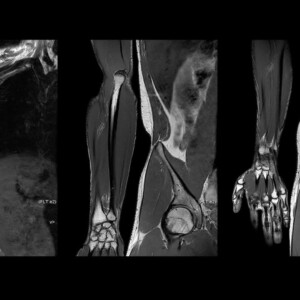

Ο τομογράφος χρησιμοποιώντας το φαινόμενο του μαγνητικού συντονισμού των μορίων νερού και σύγχρονα υπολογιστικά συστήματα δημιουργεί εικόνες εγκάρσιες, επιμήκεις και 3D του ανθρώπινου σώματος.

Σε αυτή την εξέταση απεικονίζεται με τη χρήση ή χωρίς σκιαγραφικού μέσου το παρέγχυμα ,τα οστά και όλες οι δομές του εγκεφάλου των νεύρων και του νωτιαίου μυελού διαγιγνώσκοντας παθήσεις όπως υδροκεφαλία, ριζίτιδες, όγκους κ.α.